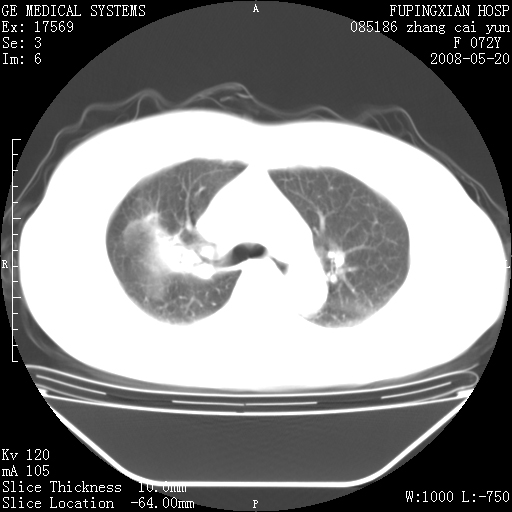

标题: CT13542:发热,咳嗽数日,经抗菌素治疗好转,请大家看排除 [打印本页]

标题: CT13542:发热,咳嗽数日,经抗菌素治疗好转,请大家看排除

上叶支气管略变窄并通畅,内壁光滑。考虑:单纯阻塞性肺炎!

右上叶支气管走行自然,未见明显管壁增厚等征像,另左主支气管起始部可见异常腔道向左侧延展左肺动脉干后方,与左下叶支气管相通,为左下叶支气管变异?

有节段性阻塞性肺炎与不张,近段支气管狭窄,周围散在肿大淋巴结影,以周围型肺癌可能性大,建议纤支镜检查。

右肺上叶实变影,内见支气管充气征,右上叶支气管通畅,肺门区未见软组织密度影,抗炎治疗有效,考虑炎症,建议继续抗炎治疗复查。

考虑为:右肺上叶感染性病变。建议:1)继续抗炎治疗后复查。2)必要时行纤支镜检查。

右上肺实变,间内有支气管充气征,考虑炎症,建议抗炎后复查